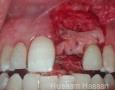

Surgery

2 Months